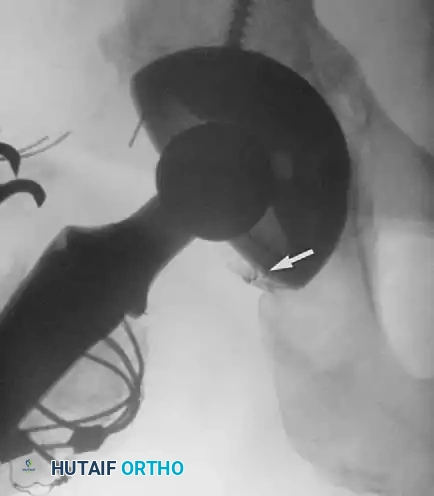

Late bleeding (≥ 1 week postoperatively) may occur secondary to a false aneurysm. In such cases, arteriography is required for the precise identification of the affected vessel, often followed by therapeutic embolization.